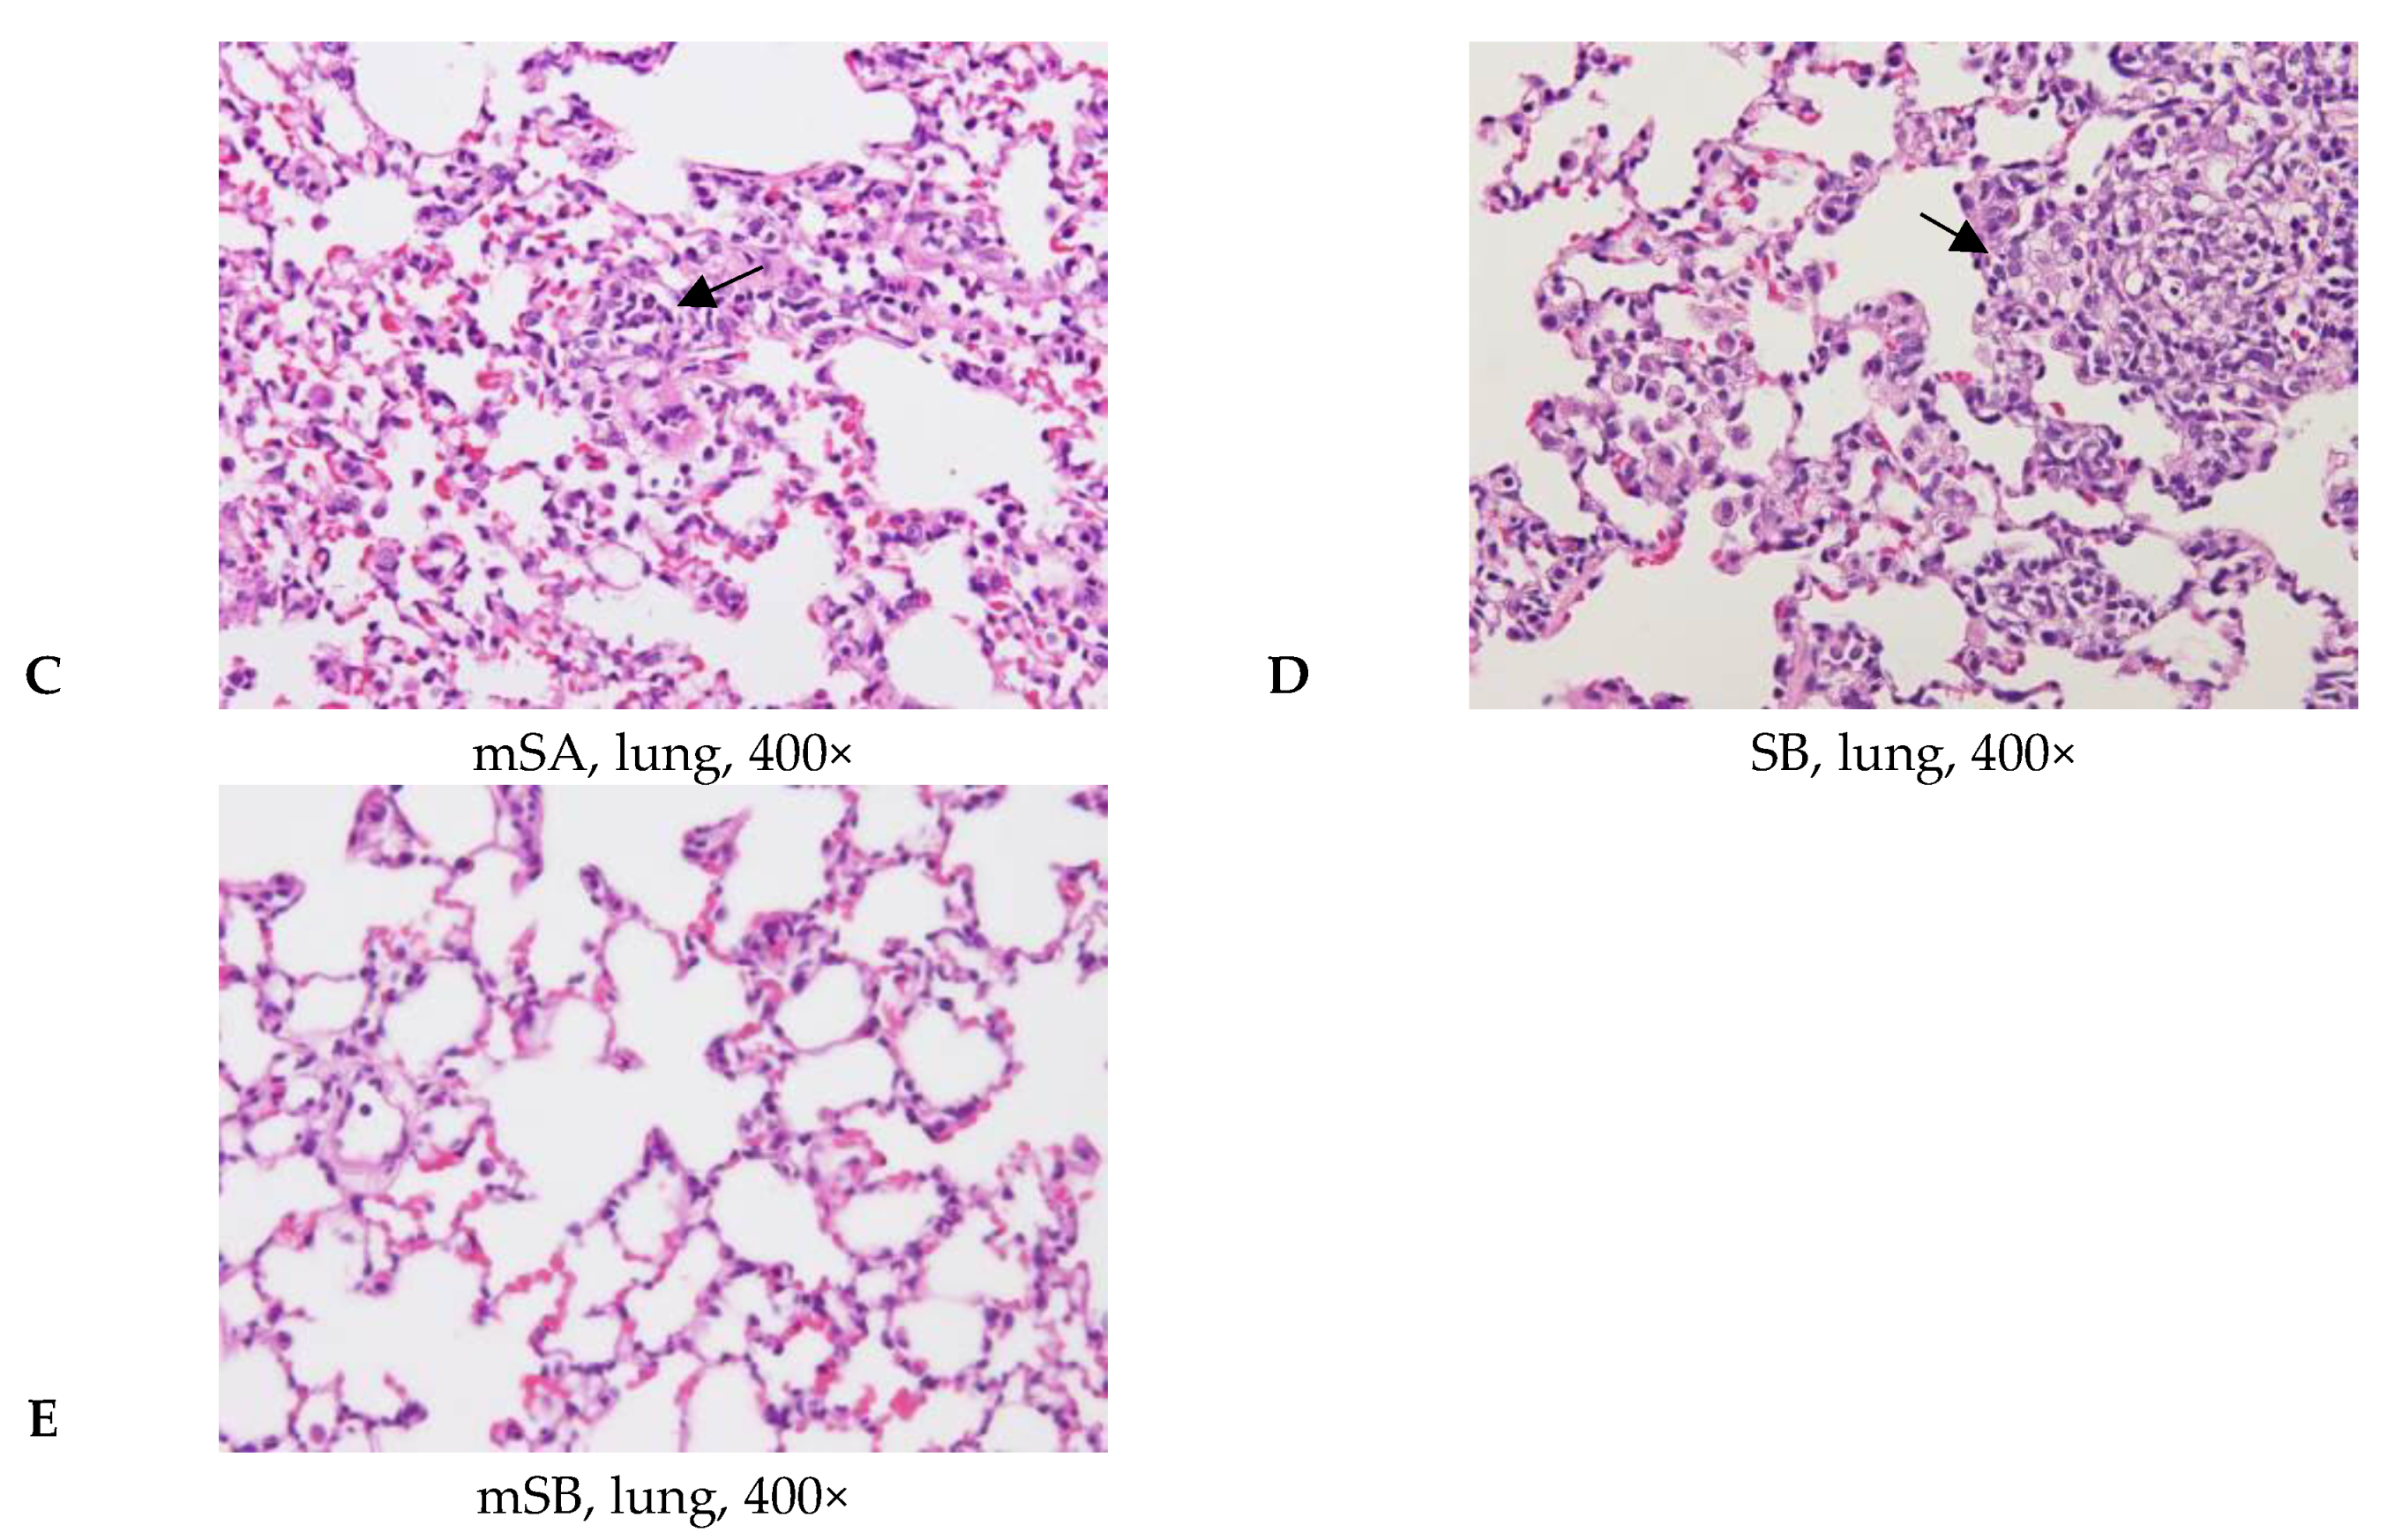

3.4. Acute Pulmonary Toxicity Test (1 D)

3.5. Acute Pulmonary Toxicity Test (14 D)